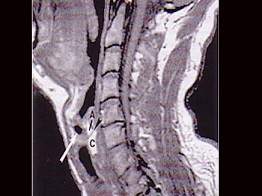

(11-13题共用题干)

男,16岁,咽异物感6年,无咽部出血及吞咽障碍。检查:舌根部中央有半球形肿物隆起,粘膜光滑,质地中等。颈部淋巴结不大:

11.MRI检查结果如下图,下一步最重要的检查是  (    )

12.本患者最可能的诊断是  (    )

13.如果碘同位素检查示舌根肿物有核素聚焦,而颈部无核素聚焦,正确的治疗是  (    )

正确答案:11.C;12.C;13.A